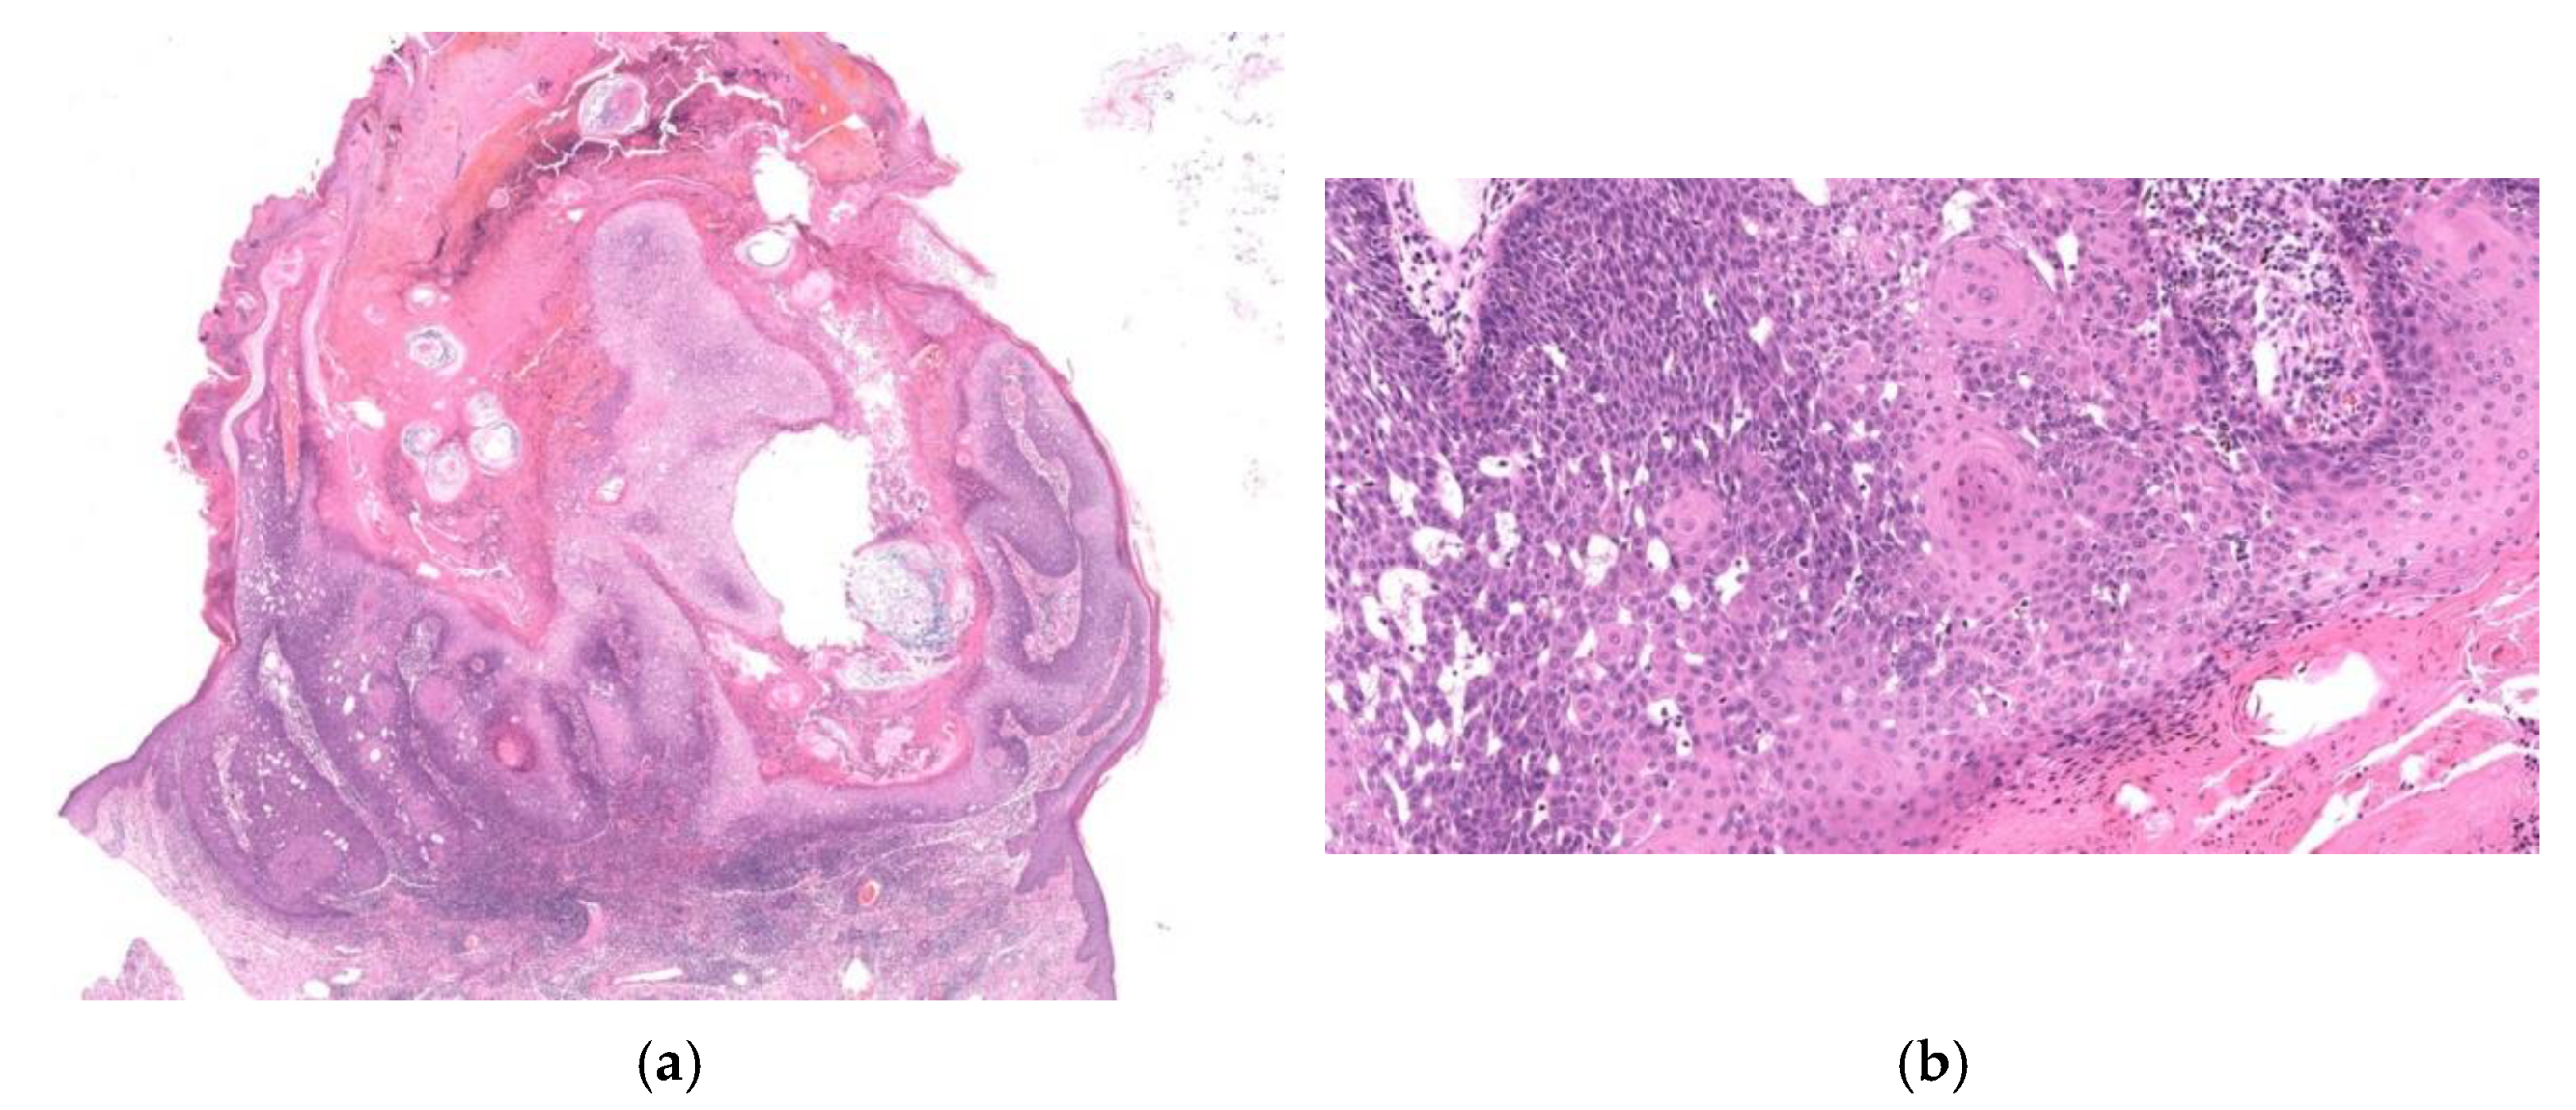

3. Diagnostically Problematic Lesions, KA with a Conventional SCC Component (KASCC)